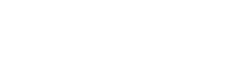

Çdo disk ka dy pjesë:

Një shtresë e fortë, e jashtme, anulus fibrosus. Pjesa e jashtme e kësaj shtrese përmban nerva. Nëse kemi dëmtim të kësaj pjese të diskut, ajo mund të bëhet mjaft e dhimbshme.

Një bërthamë të butë, Nucleus pulposus. Kjo pjesë e diskut përmban proteina që mund të shkaktojnë indet që prekin të bëhen të fryrë dhe të butë. Nëse këto proteina rrjedhin nga nervat e shtresës së jashtme të diskut, ato mund të shkaktojnë shumë dhimbje.